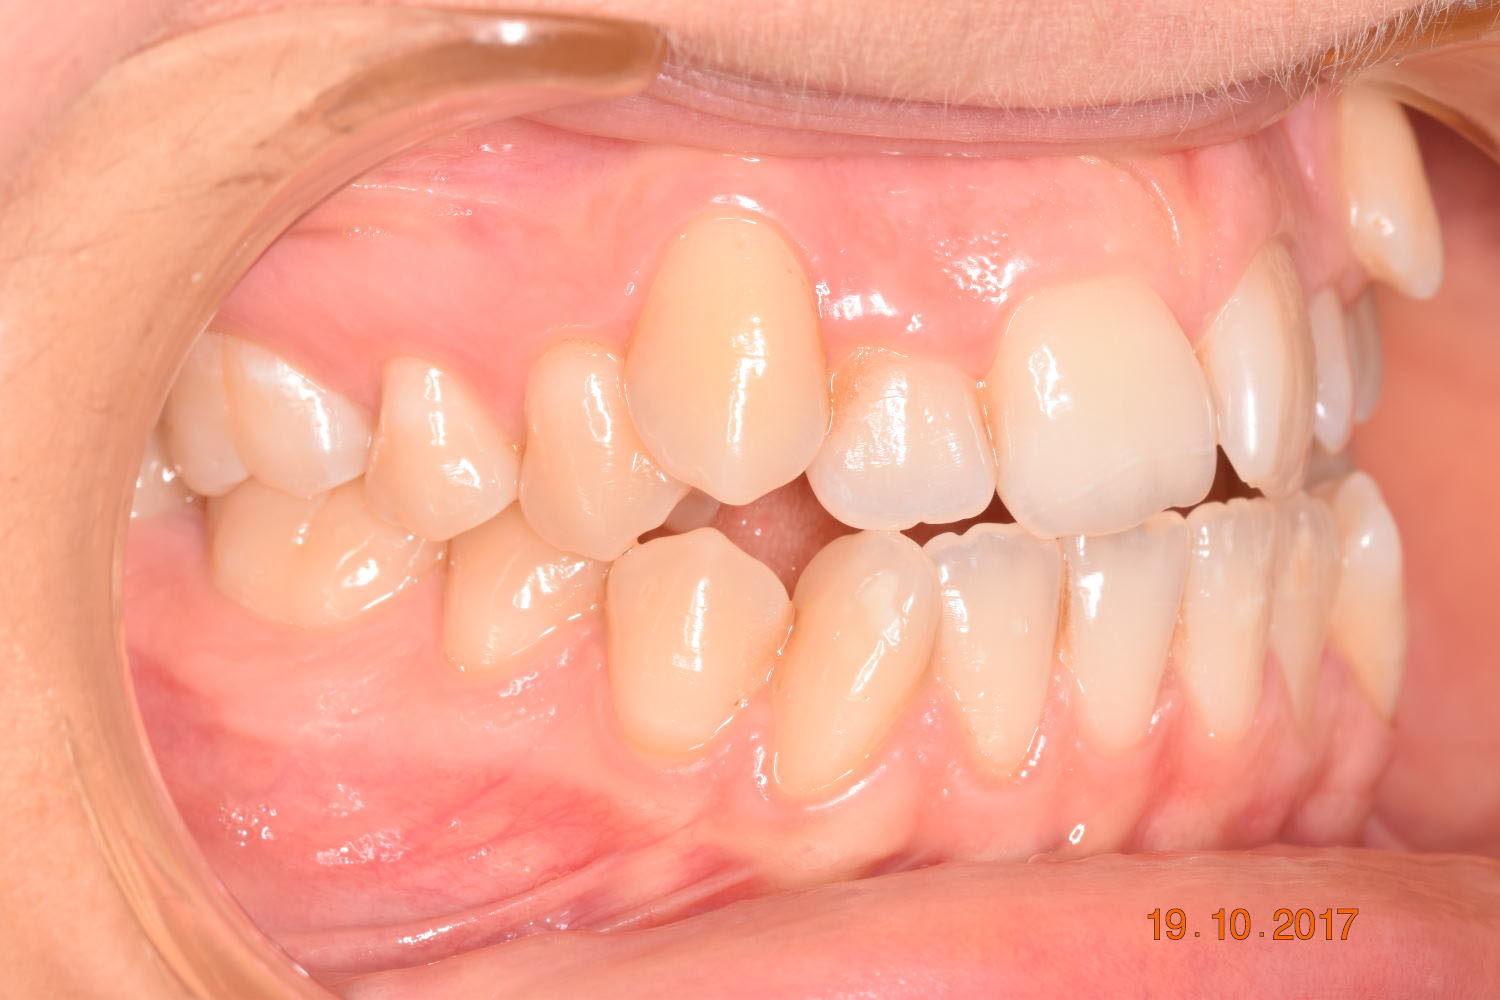

A 27-year-old female patient presented with class III malocclusion, 15 mm crowding in the upper arch, an anterior open bite, a lateral crossbite, and a total ABO score of 29. Her facial profile was straight with a retrusive maxilla, and the upper and lower incisors were retroclined. An extreme lack of midface support was also noted, and the constricted dental arches resulted in a poor smile width and dark buccal corridors. No myofunctional investigations were performed at the time, as they were initially considered unnecessary.

Adhering to the principles of Face First Orthodontics, the primary objective was to increase midface support by expanding the upper maxilla, fixing the cross bite, and aligning the teeth. Closing the open bite was a secondary objective.

Dr. Coca’s treatment plan followed the Biology First Orthodontics approach, which aims to minimize biological interventions. The treatment plan avoided extractions, stripping, TADs, corticotomy, and RPE. Given the facial requirements, a non-extraction treatment option was chosen.